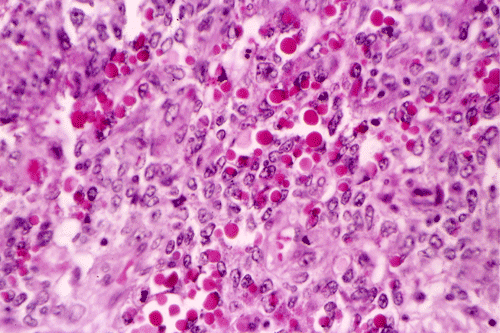

A survey at low-magnification shows a necrotic neoplasm (Panel F). The tumor cells arrange in different patterns. The tumor cells are densely packed in some areas but loosely packed in other areas.  At medium-magnification, several different patterns of architecture are disclosed. The most commonly encountered pattern in this case is a reticular-microcystic arrangement of cells (Panel G). In a significant amount of other areas, there are hypocellular to myxoid non-neoplastic stroma lined by a single layer of neoplastic cells (Panel H, I). The tumor cells have moderate to large nuclei with substantial pleomorphism. The chromatin is clumpy and hyperchromatic (Panel J). In some areas the tumor cells has an hepatoid appearance featured by a smaller nuclei with substantial amount of amphophilic cytoplasm (Panel K). Schiller-Duval bodies are occasionally noted (Panel L). A variable number of eosinophilic globules are also present and they are strongly positive for periodic acid-schiff (PAS) reaction (Panel M). Results of immunohistochemistry are as follows:

Yolk sac tumor arising in the thymus often have extensive invasion into the adjacent tissue. In this cases, the tumor is still confined. The histology is quite typical for a yolk-sac (endodermal sinus) tumor. The reticular-microcystic pattern being illustrated here is the most common pattern being encountered.  Only a small number of Schiller-Duval bodies are present. The large cells with hepatoid look correspond to the hepatoid pattern in yolk sac tumor. The solidly arranged sheets of tumor raise the possibility of an embryonal carcinoma. However, the nuclear pleomorphism, although significant, is still short of that from embryonal carcinoma. The extracellular, PAS(+), eosinophilic hyaline globules are also typical for yolk sac tumor. These globules are often immunoreactive for a-fetal protein and a-1-antitrypsin. In our case, they are only positive for a-1-antitrypsin. The lack of CD30 immunoreactivity, again, does not support a diagnosis of embryonal carcinoma.

Yolk sac tumor often, but not always, contains bright, eosinophilic globules. These extracellular, small, round, brightly eosinophilic, hyaline, strongly PAS-positive, diastase-resistant globules or droplets are most often associated with the microcystic-reticular pattern and endodermal sinus pattern. These globules are considered to be secreted by the tumor cells and accumulate within the cytoplasm. As the amount of secretion increases, the cell become distended and ruptures, discharging its contents into the surrounding tissue. Although characteristic, these eosinophilc hyaline globules are not diagnostic of yolk sac tumor because they are also found in other malignant tumors particularly those with poor differentiation. When they are present in specimen from fine needle aspiration, as in our case, they are metachromatic and provide a good clue for diagnosis 19, 20.

Immunohistochemically, yolk sac tumors are often, but not always, positive for a-fetal protein, placental alkaline phosphatase, and cytokeratin. A small number of yolk sac tumors may be immunoreactive for CD30 and raise the possibility of embryonal carcinoma. The eosinophilic globules are often immunoreactive for a-fetal protein or a-1-antytrypsin or both. Yolk sac tumors are not immunoreactive for human chorionic gonadotrophin 3. Demonstration of a-fetal protein and a-1-antitrypsin in yolk sac epithelium further support that these tumors phenotypically recapitulate the yolk sac 26.